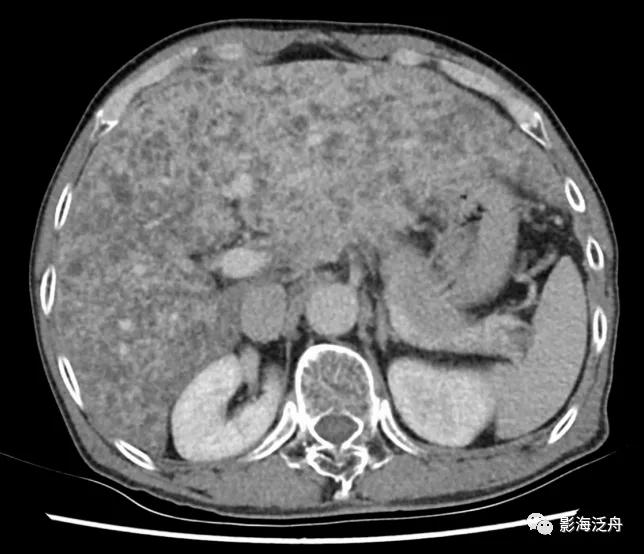

增强动脉期,患者肝实质呈弥漫性斑点状强化(类似于粟粒型肺结核),这种强化方式可能与动脉及门脉的细小分支异常分流及部分肝组织灌注不良有关。门脉期及静脉期患者肝实质呈较均匀强化(未给出图像),提示病程相对可逆。

与正常人对比可以更好地观察上述图像特征,注意肝损伤患者的肝脏强化程度整体较低(以脾脏强化程度作为参照,两幅图像的强化时间大致相仿),但平衡期强化程度并无异常减低(未给出图像)。